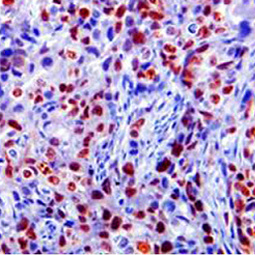

Cancer Biology

Cancer is a multistep process during which cells acquire a series of mutations that eventually lead to unrestrained cell growth and division, inhibition of cell differentiation, evasion of cell death and immune surveillance, and acquisition of angiogenic and metastatic abilities. Understanding human cancers and developing strategies for treating specific cancers has been at the forefront of biology for many decades. The nature of investigations into this area continues to evolve as we understand more properties and behaviors of cancer cells. Our researchers strive to expand their understanding of cancer biology and translate these discoveries into novel cancer therapeutics. Areas of research include cancer cell signaling, cancer stem cells, genome instability, mechanisms of DNA repair, cancer immunology and immunotherapy, inflammation and cancer, microbiome, interactions between tumor cells and stromal components, chemotherapy and mechanisms of drug resistance. Students pursue cancer research in these labs get exposed to cutting-edge technologies such as confocal microscopy, single cell sequencing, genomic and proteomic analysis, bioinformatics and data mining, a variety of model systems such as 3D-culture system, genetically engineered zebrafish and mouse models.